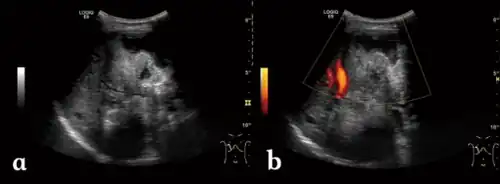

| a) Irregular type heterogeneous mass lesion b)no obvious blood flow signal | |